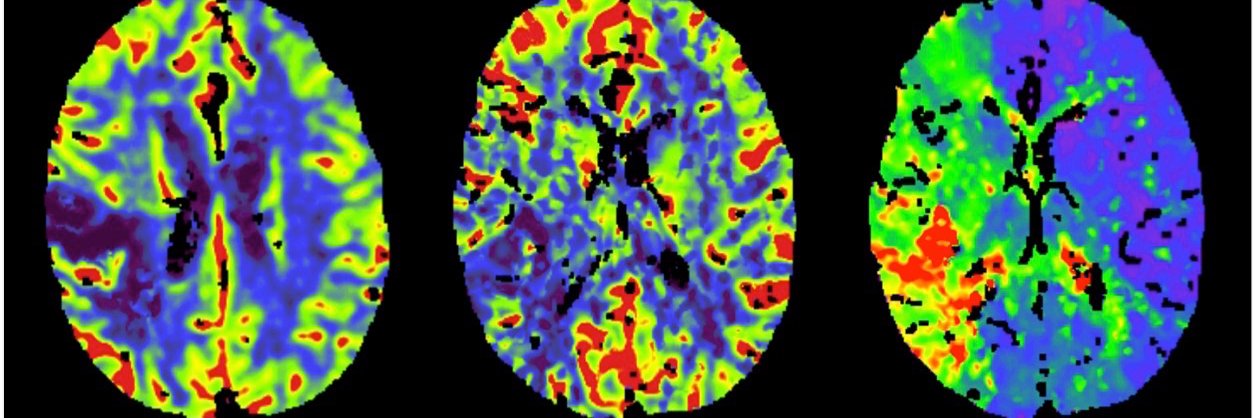

[1/3] LUMEN, a #DL pipeline for the 3D morphological analysis of lenticulostriate arteries from 7T MRI, published today by @ElsevierConnect, reseach lead by @li_rl574, an amazing collaboration with @CamStroke and @c_t_rodgers from @Cambridge_Uni ➡️ Paper: lnkd.in/et58aRt5